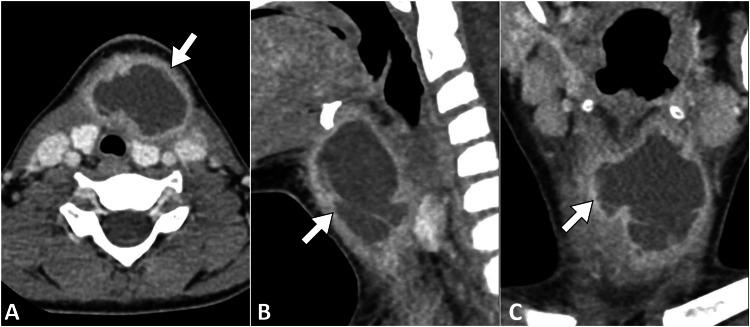

Pediatric neck masses present a diagnostic challenge, encompassing various etiologies, including rare entities like branchial cleft anomalies. Branchial cleft cysts, resulting from incomplete embryonic cleft obliteration, may become symptomatic. This case report describes a seven-year-old boy who presented with a week-long history of fever and progressively enlarging left anterior cervical swelling. Physical examination revealed a fluctuant, non-tender mass, prompting diagnostic investigations. Laboratory results indicated an elevated white blood cell count and inflammatory markers. Computed tomography identified a hypodense, rim-enhancing mass consistent with an abscess secondary to a fourth branchial cleft cyst. Ultrasound-guided aspiration yielded purulent material, confirming infection. This case highlights the clinical significance of fourth branchial cleft cysts as rare inflammatory neck masses in pediatric patients. The embryological context informs their diverse anatomical manifestations. Surgical excision remains the primary treatment, demanding consideration of anatomical complexities.